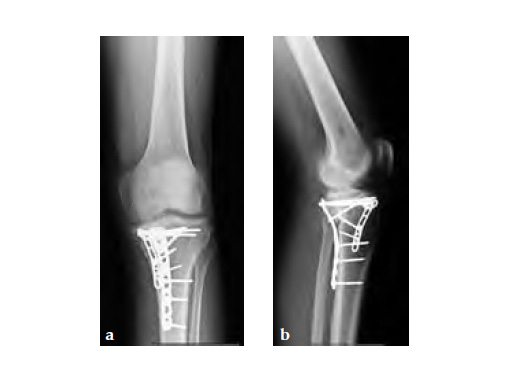

The system consists of six anatomically precontoured plates (1, 2, 4, 6, 8, or 10 shaft holes) with a range of six lengths (72-186 mm). The low profile plate head limits soft-tissue irritation and features four locking holes; one slotted for ease of plate positioning. The 3.5 mm LCP holes in the shaft enable fixation of posteromedial fragments with locking or non-locking screws.

Postoperative healing was uneventful and the patient had no complications.